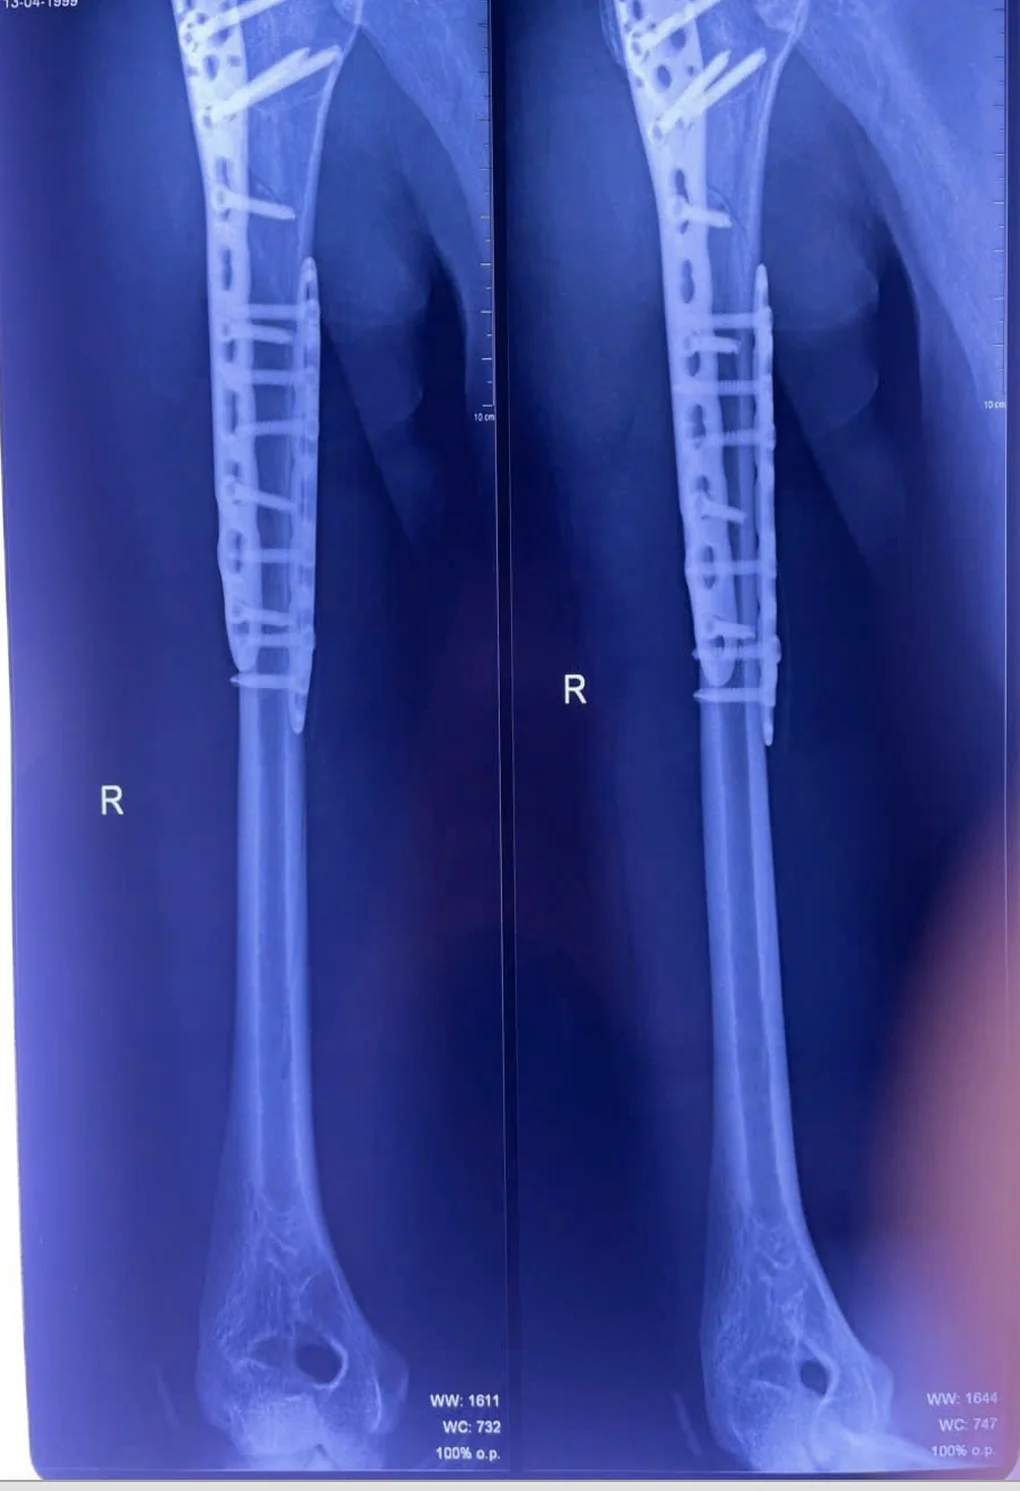

Sau phẫu thuật, vị trí gãy xương cánh tay được cố định vững chắc. (Ảnh: BVCC)

“Kỹ thuật kết hợp xương ít xâm lấn giúp giảm tổn thương mô mềm, hạn chế mất máu và nguy cơ nhiễm trùng, đồng thời mang lại hiệu quả giảm đau, rút ngắn thời gian hồi phục và nằm viện cho người bệnh”, BS.CKI Sơn Tấn Ngọc, người trực tiếp thực hiện ca phẫu thuật chia sẻ thêm.

Suốt gần 3 giờ, ê-kíp khoa Chấn thương chỉnh hình đã thực hiện thành công ca phẫu thuật. Ổ gãy được xử lý triệt để, rửa sạch, loại bỏ máu tụ, nắn chỉnh và cố định bằng nẹp titan cùng vít khóa.

Dưới sự hỗ trợ của hệ thống C-arm hiện đại, cấu trúc xương tại vị trí tổn thương của bệnh nhân được cố định vững chắc và các đầu vít không ảnh hưởng đến mặt khớp.